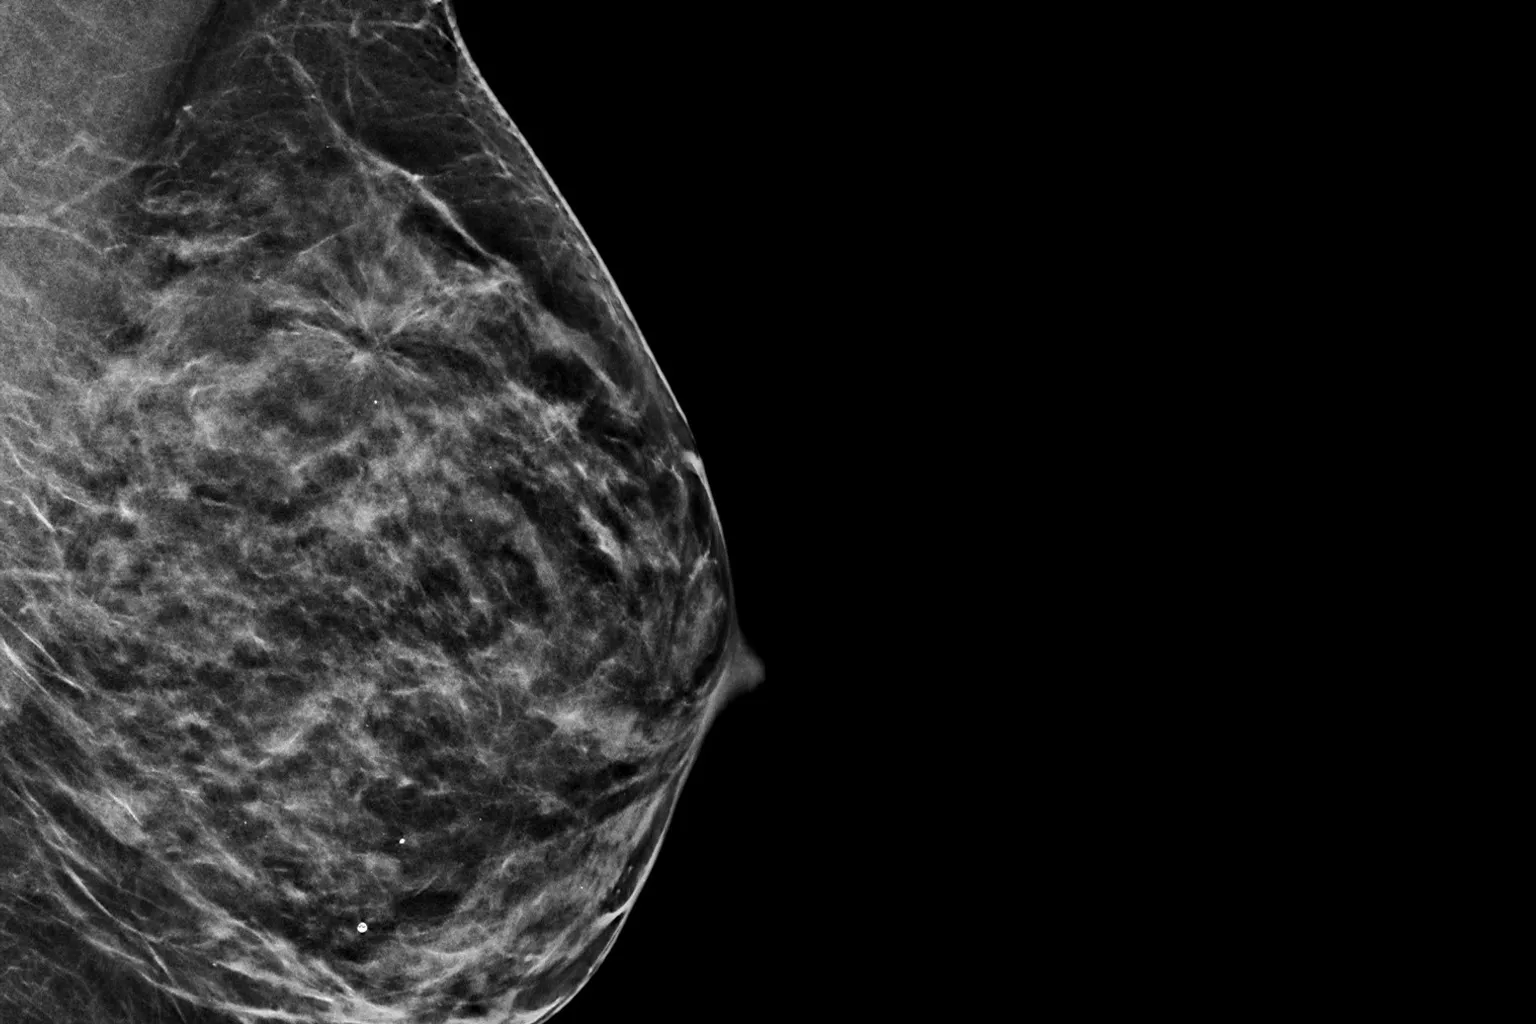

Clarity HD Yüksek Çözünürlüklü Görüntüleme ile Tanıda Netlik

Clarity HD™ teknolojisi, Hologic’in dijital mamografi sistemlerinde yer alan yüksek çözünürlüklü 3D görüntüleme teknolojisidir. Bu sistem, meme dokusunu 70 mikron çözünürlükle katman katman tarayarak olağanüstü netlikte tomosentez görüntüleri sunar. Sonuç: daha doğru tanılar, daha az tekrar çekim ve daha güvenli tarama kararları.

Özellikle yoğun meme dokusuna sahip hastalarda, Clarity HD, dokuların üst üste binmesini önleyerek küçük kitleler, gizli kalsifikasyonlar ve diğer anormalliklerin (örneğin spiküler lezyonlar veya distorsiyonlar) daha görünür hale gelmesini sağlar. Bu da erken evre meme kanserinin tespiti açısından kritik öneme sahiptir. Geleneksel 2D sistemlerle karşılaştırıldığında, Clarity HD ile elde edilen görüntü netliği %50’ye kadar artarken, belirsiz tanılar nedeniyle istenen ileri görüntüleme oranları %40’a kadar azalmaktadır.